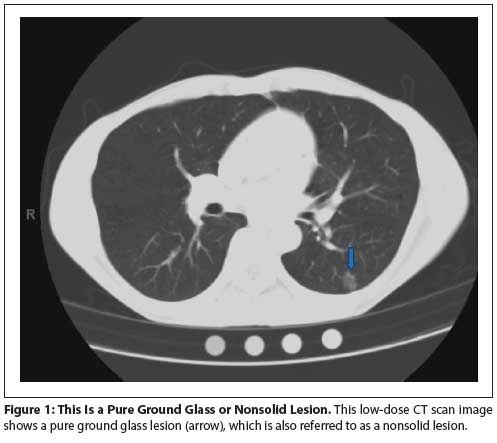

Figure 1: This Is a Pure Ground Glass or Nonsolid Lesion.

Nonsolid or ground glass nodules (see Figures 1 and 2) are not very dense. Lung structures such as airways and blood vessels can be seen through them on CT scans.[8,21,22] Small ground glass lesions are difficult to biopsy and are not amenable to functional imaging. Ground glass lesions ≤ 10 mm are rarely cancerous. Ground glass lesions that persist over time are more likely to be malignant. Mixed lesions that have a solid component are more likely to be cancerous (see Figures 3 and 4).

Figure 1 illustrates the appearance of ground glass or nonsolid nodules. These lesions often resolve. The algorithm in Figure 2 highlights appropriate management.[20,34,35] Lesions

≤ 5 mm warrant LDCT every 12 months. They should be resected for an increase in size or a change in character. Ground glass or nonsolid nodules between 5 mm and 10 mm in size should undergo a repeat LDCT in 6 months. An increase in size or change in character warrants resection. Stable lesions should be followed with annual LDCT. Ground glass or nonsolid lesions > 10 mm should be reassessed with LDCT in 3 to 6 months. Those that are increasing in size or changing in character should be resected. Those that are stable should be evaluated with LDCT every 6 to 12 months or biopsied or resected.